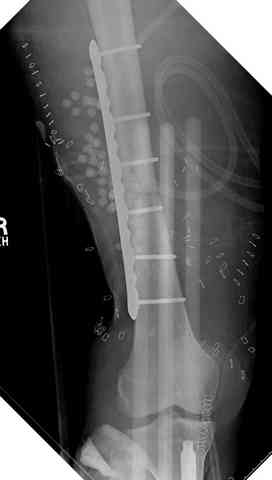

здесь случай с политравмой, перелом зафиксирован  наружным

фиксатором, после третьей irrigation&debridment фиксация бедра

пластиной с последующей кожной пластикой.

Вложение не в текстовом формате было извлечено…

Имя     : 2 open femur 3.jpg

Тип     : image/jpeg

Размер  : 13057 байтов

Описание: отсутствует

Url     : http://weborto.net:8080/pipermail/ortho/attachments/20080516/ebe5bb74/attachment-0012.jpg